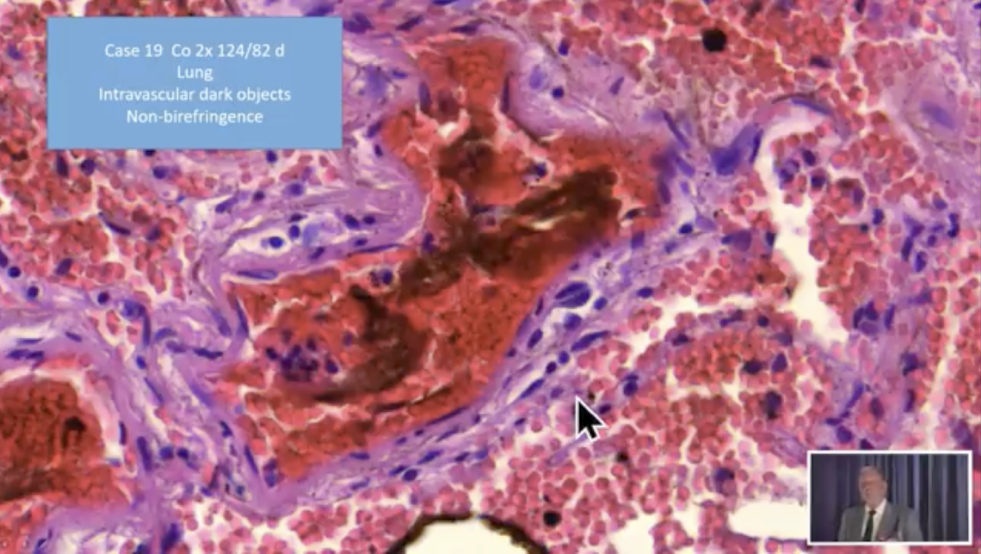

Video 9.10.2021: Pfizer

vaccine=toxic agent! -

Pfizer-Impfstoff=Kampfstoff! Objekte+Fäden

(25''): https://www.bitchute.com/video/YqnKldt4iyOH/

Pfizer-Impfstoff=Kampfstoff! (25'')

Link: https://www.bitchute.com/video/YqnKldt4iyOH/

- Bitchute-Kanal: NatMed-etc. - hochgeladen am

10.10.2021